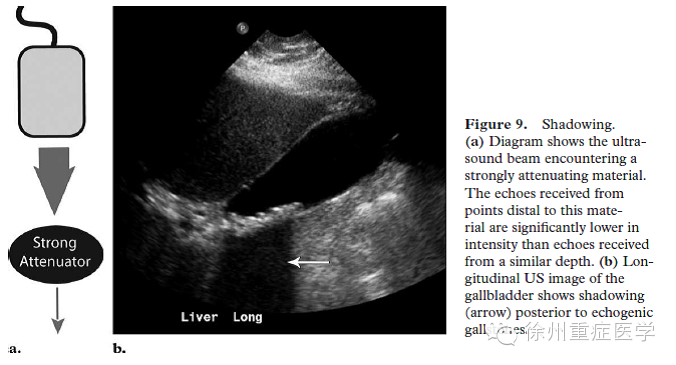

当超声波遇到反射体时,较周围组织反射越强则向远处传播的声波强度越弱,反之,反射越弱,向远处传播的声波强度越强。因此,当声束遇到高衰减或强反射体时,向远处传播的声波振幅明显减低(Fig

9a),从远处组织返回的回波也会消失。临床上,表现为高衰减或强反射后无回声或低回声带,称为声影(shadow(Fig 9b)